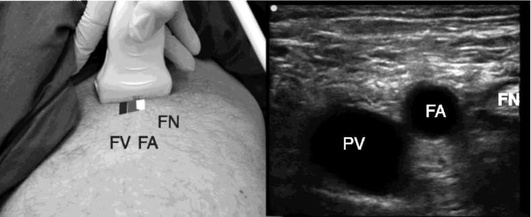

Катетеризация центральных вен

Показания к установке центрального венозного катетера (ЦВК).

1. Потребность во введении инфузионных сред или лекарственных препаратов при невозможности обеспечения требуемого объема, скорости, эффективности и безопасности инфузионной и/или медикаментозной терапии за счет катетеризации периферических вен и/или внутрикостного введения.

2. Гемодинамический мониторинг (баллонные, термодилюционные и другие методы мониторинга).

3. Проведение длительной вазопрессорной, инотропной, противоаритмической и химиотерапии.

4. Проведение ЗПТ и других способов экстракорпоральной гемокоррекции.

5. Проведение экстракорпоральных методов поддержки кровообращения и дыхания.

6. Эндокардиальная кардиостимуляция.

7. Введение гиперосмолярных и/или обладающих раздражающим и/или повреждающим действием растворов (в том числе ПП).